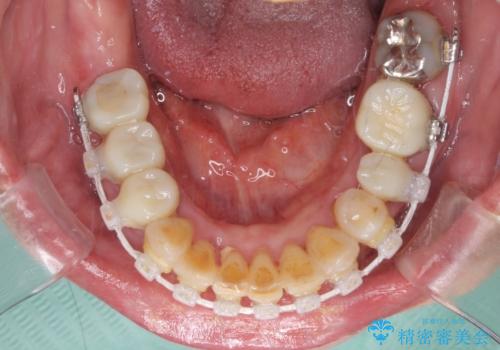

歯肉の状態が落ち着いた後に下顎の矯正治療を行い、その後補綴治療を行うこととしました。

ワイヤー矯正の注意事項(リスク・副作用など)

- 治療中は違和感や痛みが起こることがあります

- 症状により、抜歯が必要な場合があります

- 治療中は歯磨きがしにくくなるため、虫歯や歯周病になりやすくなります

- 矯正治療後の保定が不十分だと後戻り(元の位置に戻ろうとする動き)をします

- 自費診療(保険適用外)となります